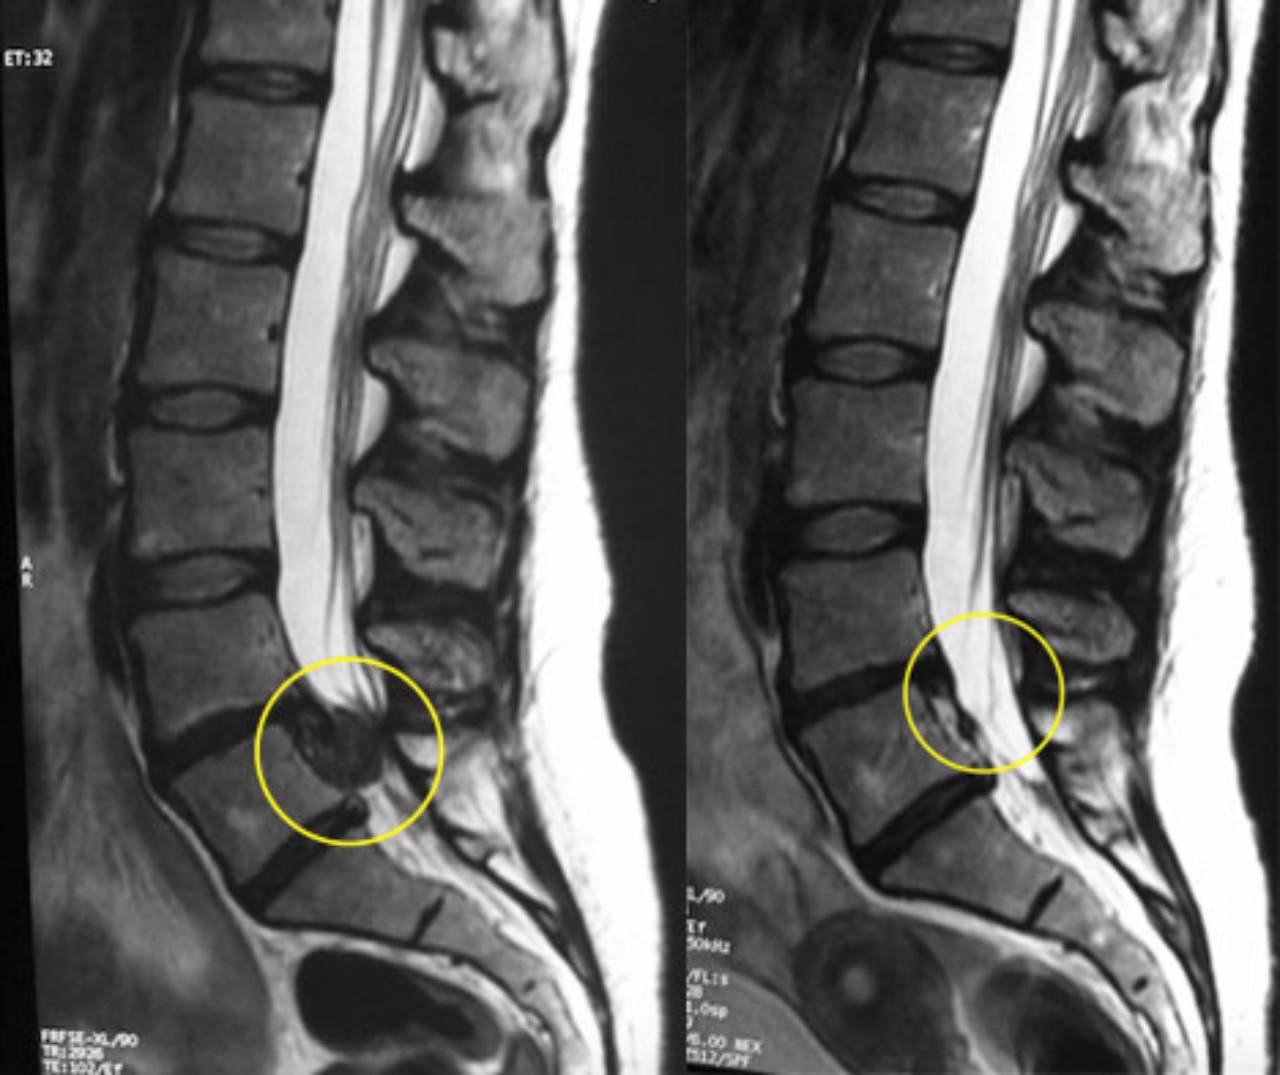

Avaliação, diagnóstico disfuncional e tratamento de discopatias degenerativas, protusões e hérnias de disco, através de técnicas de terapias manuais e exercícios corretivos.